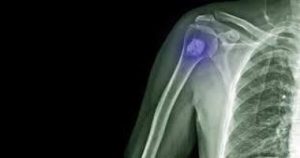

La metástasis ósea

En el último episodio de Artro Esport Podcast, explicamos qué es la metástasis ósea: cuál es su origen, cómo se trata y cuál suele ser el perfil del paciente. Descubre